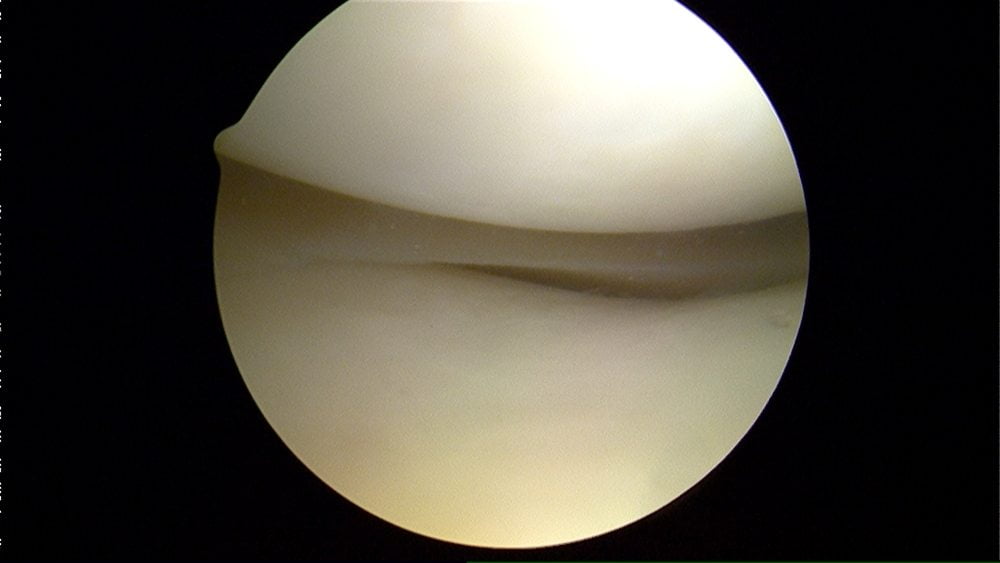

Артроскопия показана для обследования внутренних поверхностей сустава. Через проколы мягких тканей в его полость вводится миниатюрное устройство с видеокамерой. Изображение с нее поступает на экран прибора. При необходимости сразу производится удаление накопившейся жидкости с дальнейшей обработкой антисептическими растворами.